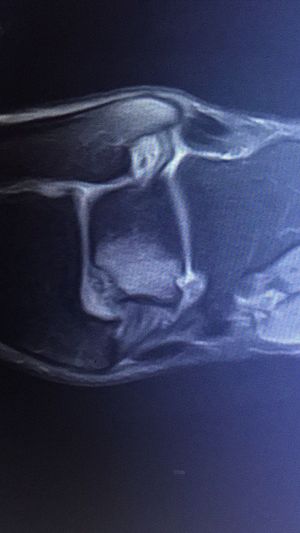

Osteochondrale Läsion